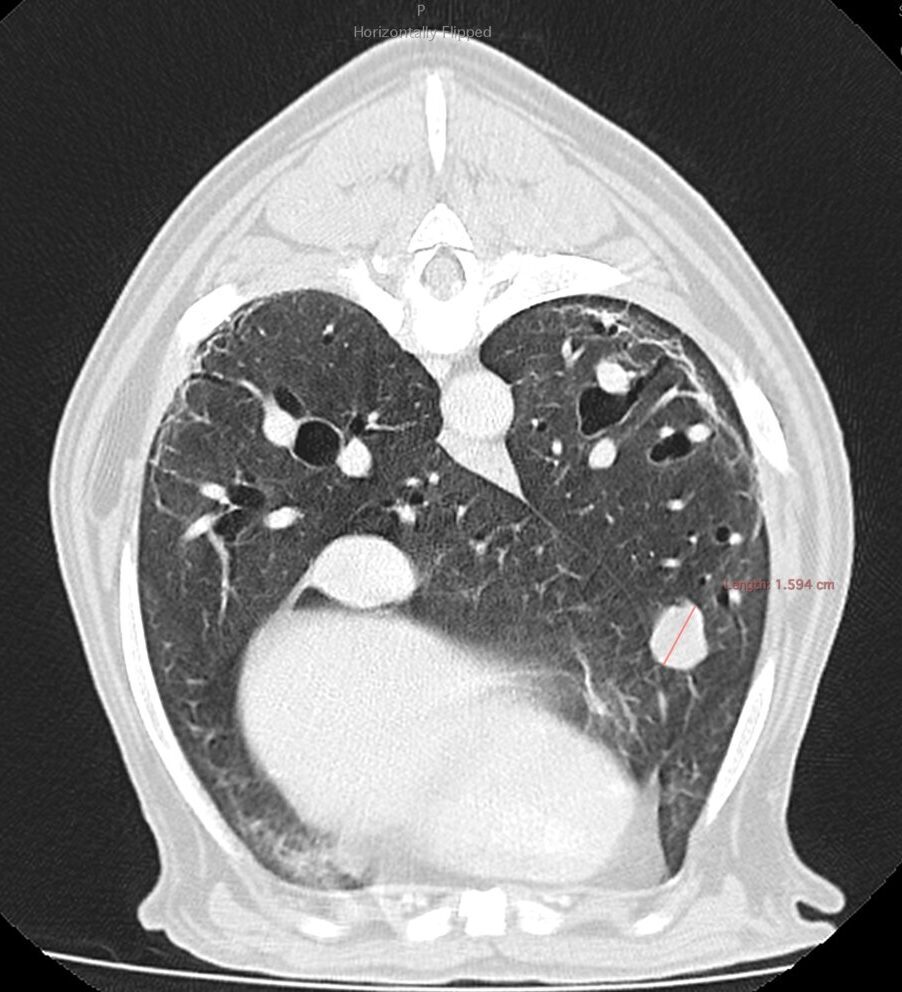

Dos semanas más tarde se realiza el TC de reestadiaje y se detecta la presencia de enfermedad metastásica en pulmón. Adicionalmente, la afectación completa del paladar y la invasión en cavidad nasal hacen que se descarte la cirugía como terapia local.

A los 18 meses del diagnóstico, los cuidadores refieren la aparición de hifema y exoftalmia en el ojo derecho, lo que sugiere metástasis, además de una masa perianal compatible con neoplasia indiferenciada (posible melanoma amelanótico). En el estudio de TC se documenta una respuesta completa de la lesión primaria y metástasis nodales y una remisión casi completa de las metástasis pulmonares (lesiones milimétricas equívocas) (imagen 1). Se realiza la resección de la masa perianal, pero los cuidadores rechazan la enucleación.

A los 28 meses se realiza un TC de re-estadiaje antes de considerar el segundo protocolo de radioterapia, donde se documenta una progresión objetiva de la masa oral y ligera progresión de la metástasis pulmonar (imagen 1).